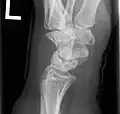

Radiographic classification

First described by David Lichtman et al. in 1977.[7] The purpose of this classification system is to guide treatment and to enable comparison of clinical outcomes.

1. Stage I Normal radiograph (possible lunate fracture).

2. Stage II Sclerosis of the lunate without collapse. (Portions of the lunate begin to deteriorate. This shows as a white blemish on x-rays.)

3. Stage IIIA Lunate collapse and fragmentation, in addition to proximal migration of the capitate.

4. Stage IIIB Lunate collapse and fragmentation, in addition to proximal migration of the capitate. In addition there is fixed flexion deformity of the scaphoid.

5. Stage IV Changes up to and including fragmentation, with radiocarpal and midcarpal arthritic changes.